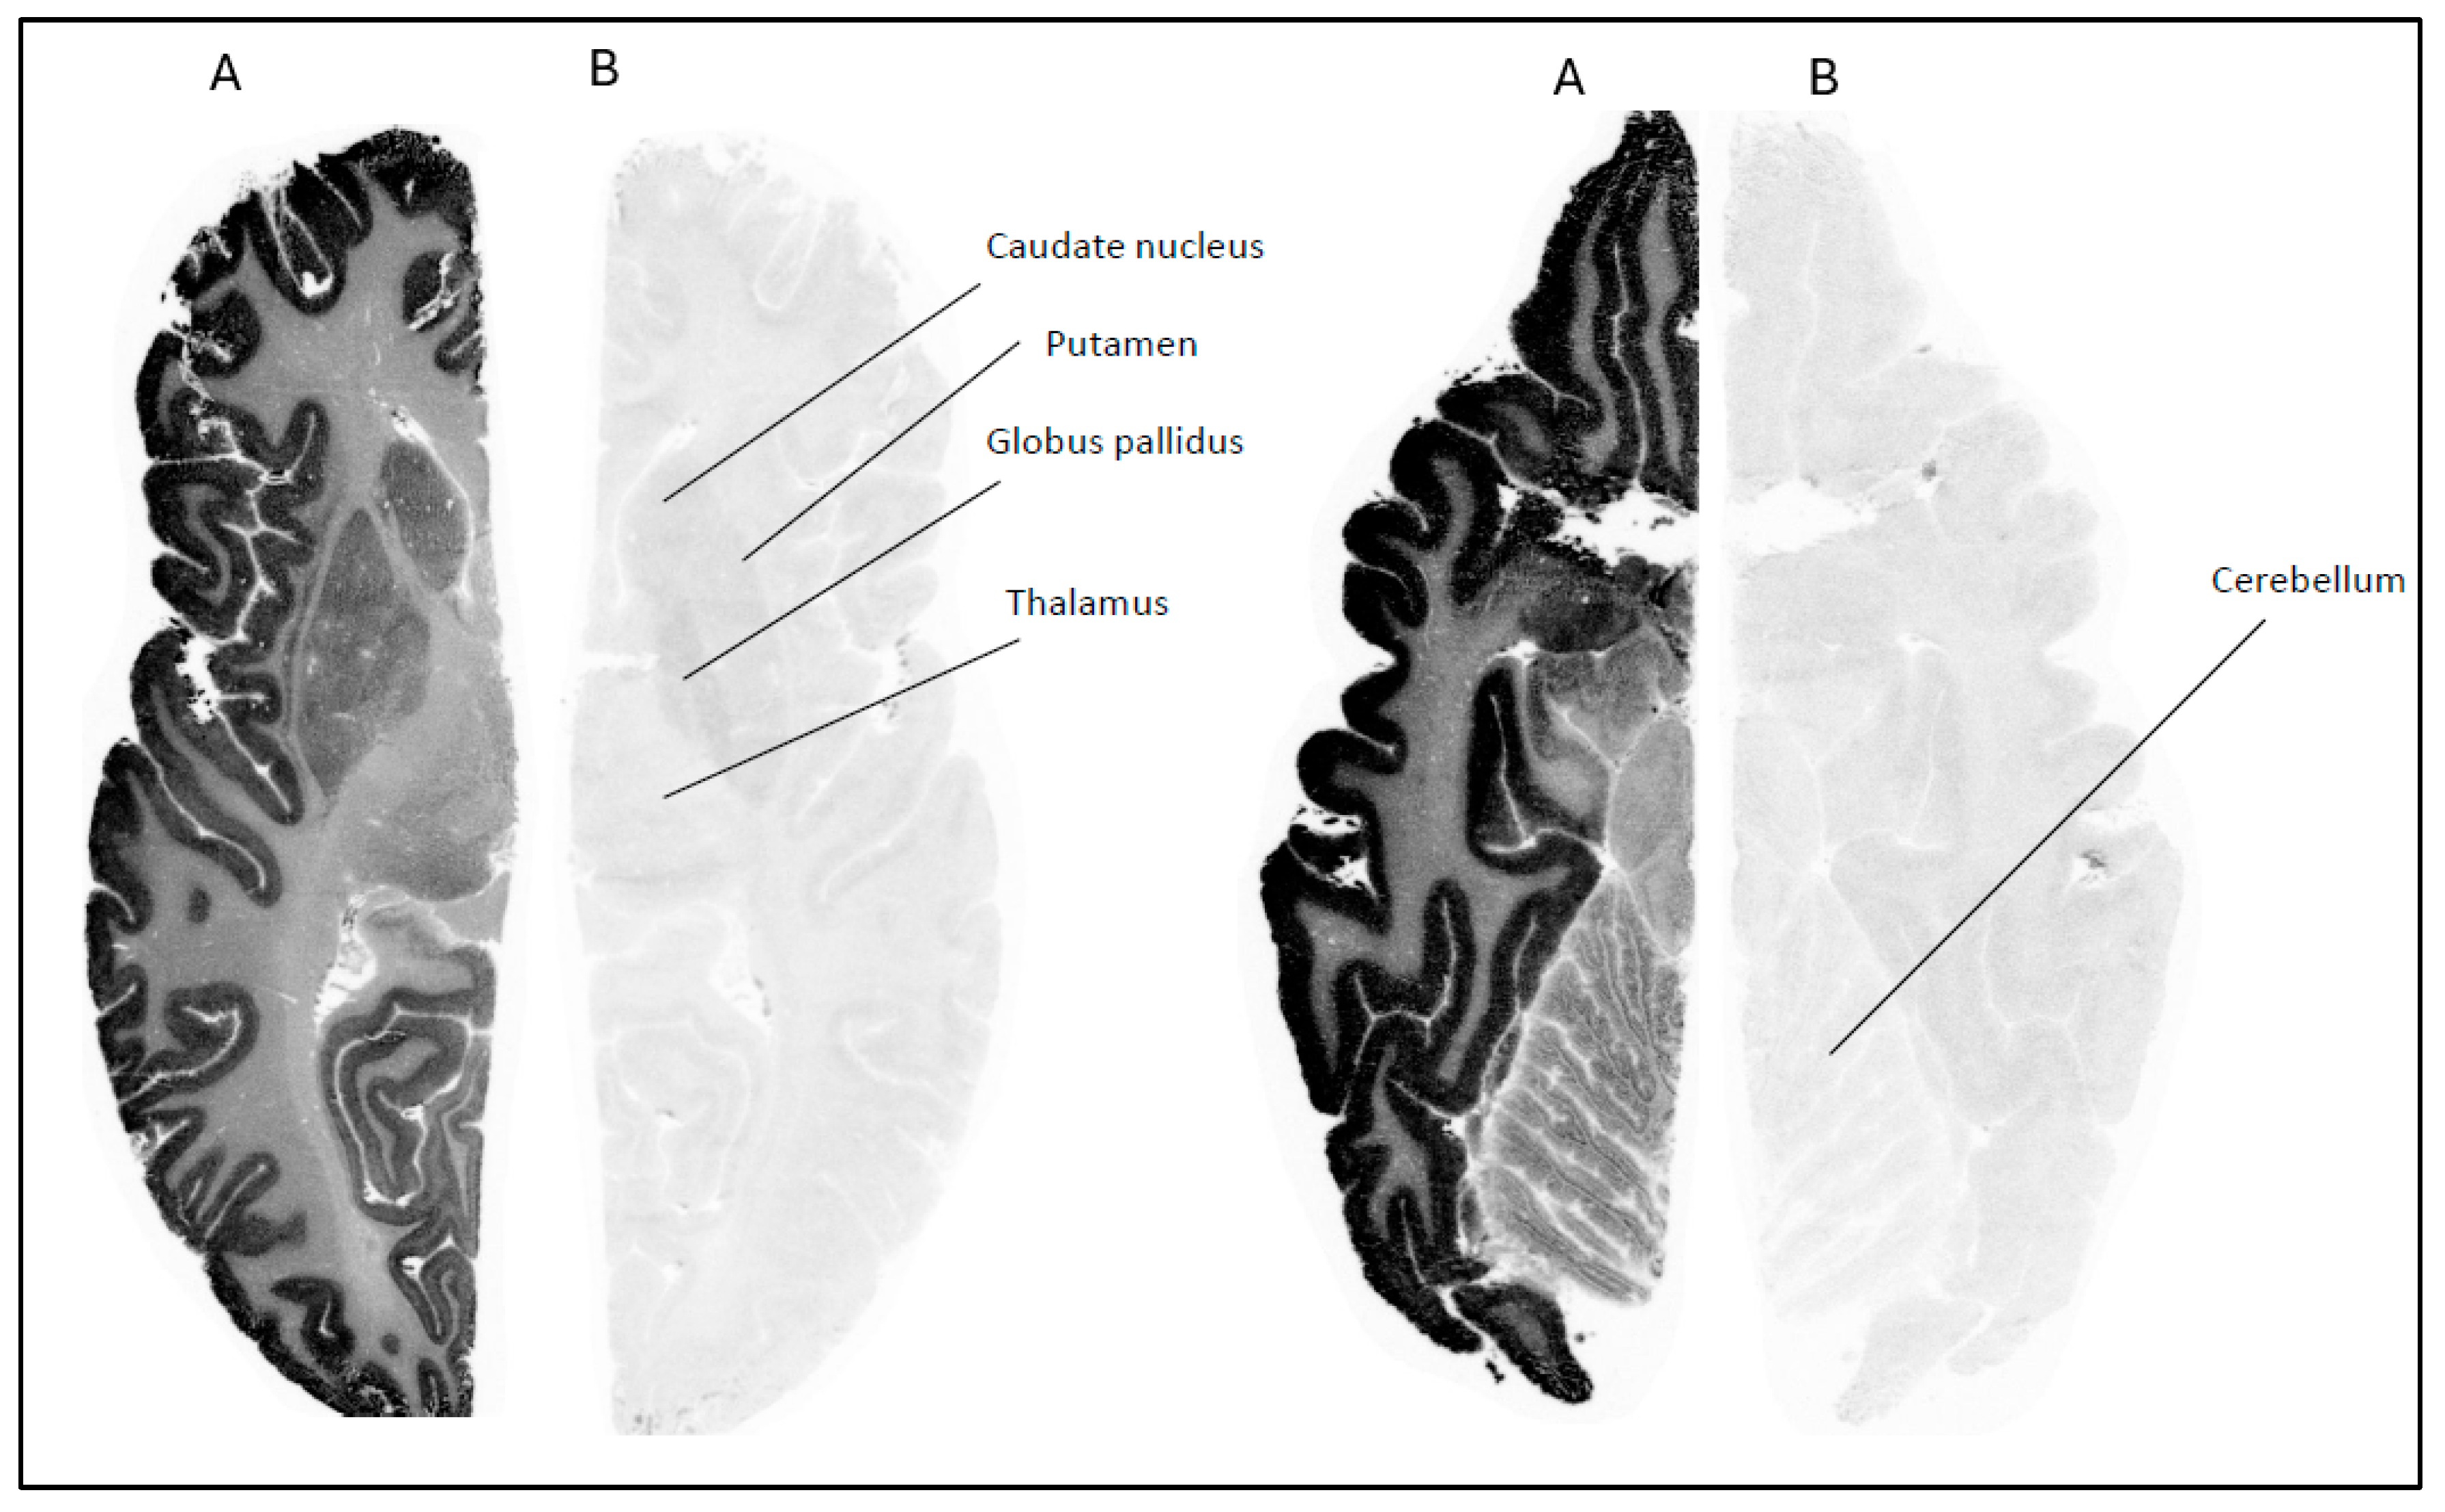

Figure 4. Autoradiograms of horizontal slices of a human brain labeled with [18F]2 at baseline condition (A) and during incubation with PFE-360 (10 µM) (B). Brain sections at the level of caudate, putamen, globus pallidus, and thalamus (left) and cerebellum (right).

In contrast, [18F]2 demonstrated a different binding profile. Its binding in human brain regions such as the striatum, hippocampus, and cerebellum was significantly reduced when sections were pretreated with 10 µM of PFE-360. The displacement of [18F]2 by PFE-360 suggests that its binding in these regions is specific to LRRK2, making it a promising candidate for further development as an LRRK2 PET imaging agent. Overall, the differential displacement profiles underscore the importance of both tracer selectivity and binding affinity in evaluating the suitability of radioligands for neuroimaging applications. Among the tested compounds, [18F]2 showed promise for targeting LRRK2 in human tissues. For radioligand [11C]3, no ARG studies were performed. Instead, we proceeded directly to in vivo PET imaging in NHPs with all three radioligands [18F]1, [18F]2, and [11C]3.